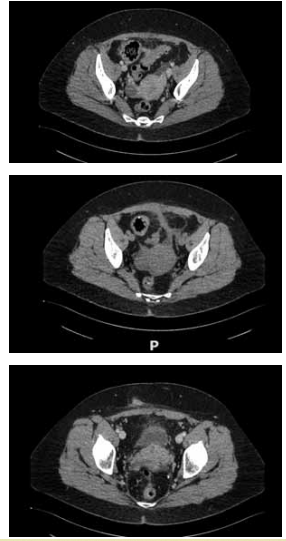

Mulher de 29 anos, submetida a bypass gástrico em Y de

Roux há 3 anos, evoluiu com boa perda ponderal e seguimento regular. Após 2 anos de cirurgia, iniciou reganho

de peso, recorrendo a um regime alimentar hipocalórico.

Iniciou episódios recorrentes de dor abdominal em andar

superior, náuseas e vômitos pós-prandiais há 2 semanas, com piora importante nas últimas 24 horas, quando

buscou o pronto-socorro. Ao exame físico, apresenta dor

em andar superior do abdome, sem sinais de peritonite.

Realizou a tomografia computadorizada demonstrada na

imagem a seguir:

(Arquivo pessoal; imagem usada com autorização)

Diante do quadro, qual a principal hipótese diagnóstica e a conduta indicada, respectivamente?

(Arquivo pessoal; imagem usada com autorização)

Diante do quadro, qual a principal hipótese diagnóstica e a conduta indicada, respectivamente?